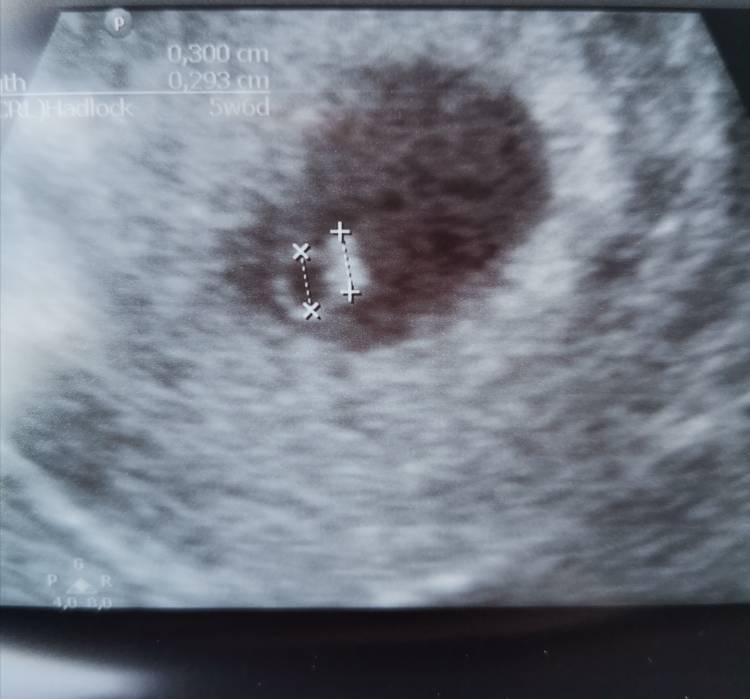

Jestem. Wszystko jest dobrze [emoji3590] serduszko bije 117 uderzeń na minutę [emoji7][emoji3064][emoji3064]

Następna wizyta 9 kwietnia. Mam juz kartę ciąży. Pęcherzyk wygląda na 6+5, a zarodek na 5+6, ale ta rozbieżność podobno wynika z tego, że przy 3 mm pomiar nie jest jeszcze idealnie dokładny i wg ginekolog mieści się w normie.

Zobacz załącznik 1254625